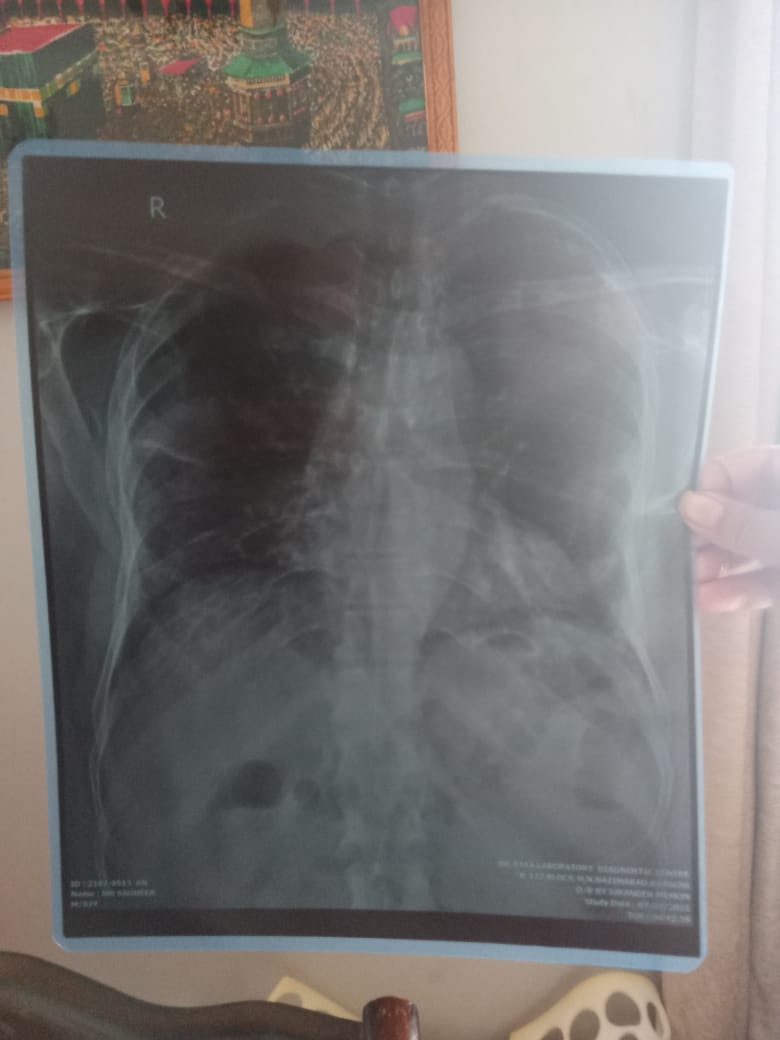

Asking for Father, Male, 65 years old, Karachi

My father has cough and chest weakness. We consulted a doctor and he suggested chest checkup. He said "it's just chest infection", we went for second opinion and the second doctor said "serious lungs infection". Please guide me, is this something serious or just chest infection? What do you suggest in this condition?

Chest infection is always serious treat it asap